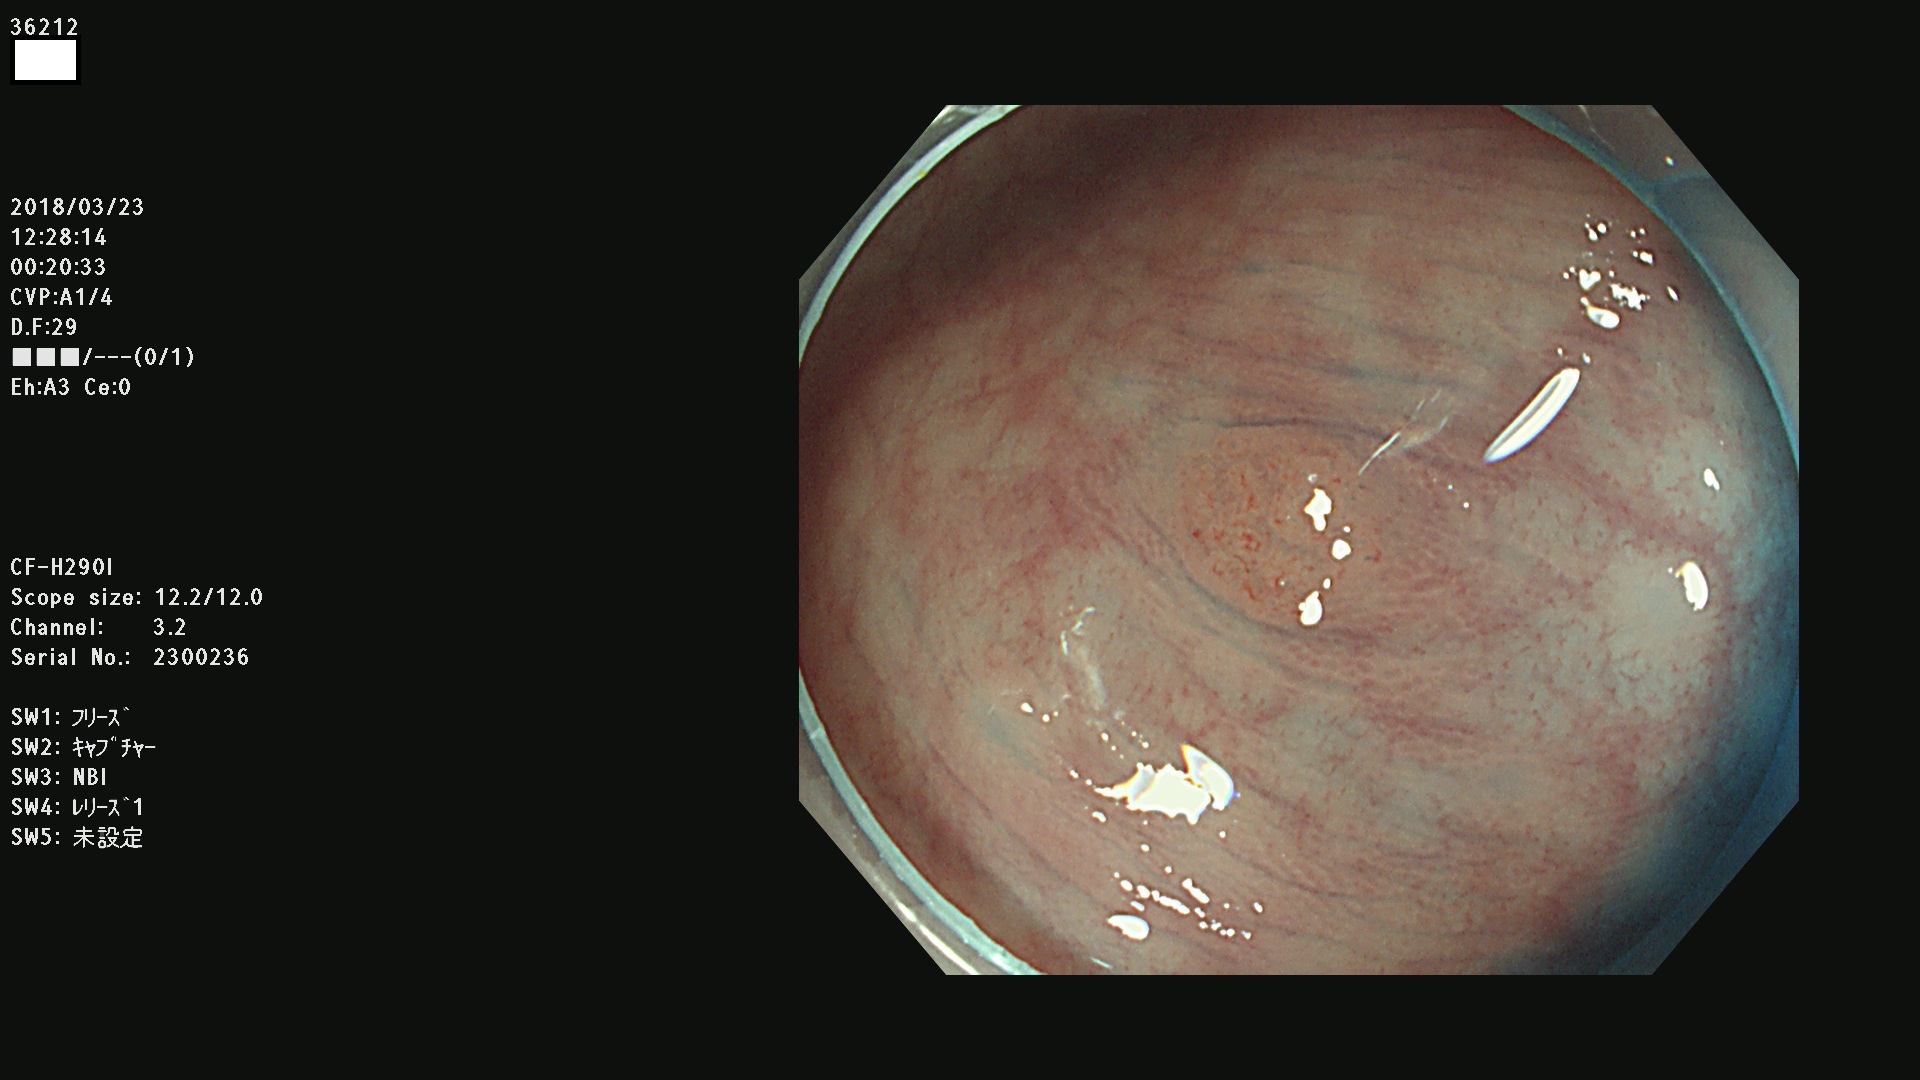

36201 36202 36203 36205 36207 36209 36210 36212 36213 36214 36215 36217 36220 36221 36222 36224 36225 36226 36227 36229 36230 36231 36232 36235 36236 36238 36240 36243 36244 36246 36247(SSAPのみ。SPS) 36248 36249 36251 36252 36253 36254 36255 36256 36257 36258 36259 36261 36262 36264 36265 36267 36269 36270 36272 36274 36275 36276 36279 36280 36281 36283 36285 36288 36289 36291 36292 36295 36296 36297 36299

発見困難で危険性の高い平坦型病変(上記100名より抽出)